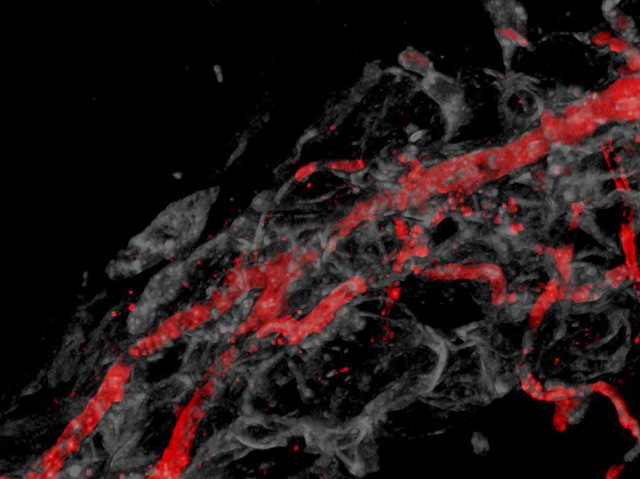

Smoking Vessels

You have tens of thousands of miles of blood vessels in your body, responsible for channelling blood cells deep into your organs to provide them with oxygen and nutrition. But just as the water pipes in a house can spring a leak if they're damaged or worn, our biological plumbing can become leaky too. Researchers are taking a closer look to work out how this happens. The red lines in this image are damaged blood vessels, and the smoke-like traces are the liquid leaking out of them. Leaky blood vessels are bad news and cause heart problems and other illnesses. And like water pooling on the floor from a broken pipe, faulty blood vessels lead to fluid collecting in the body – a condition known as oedema.